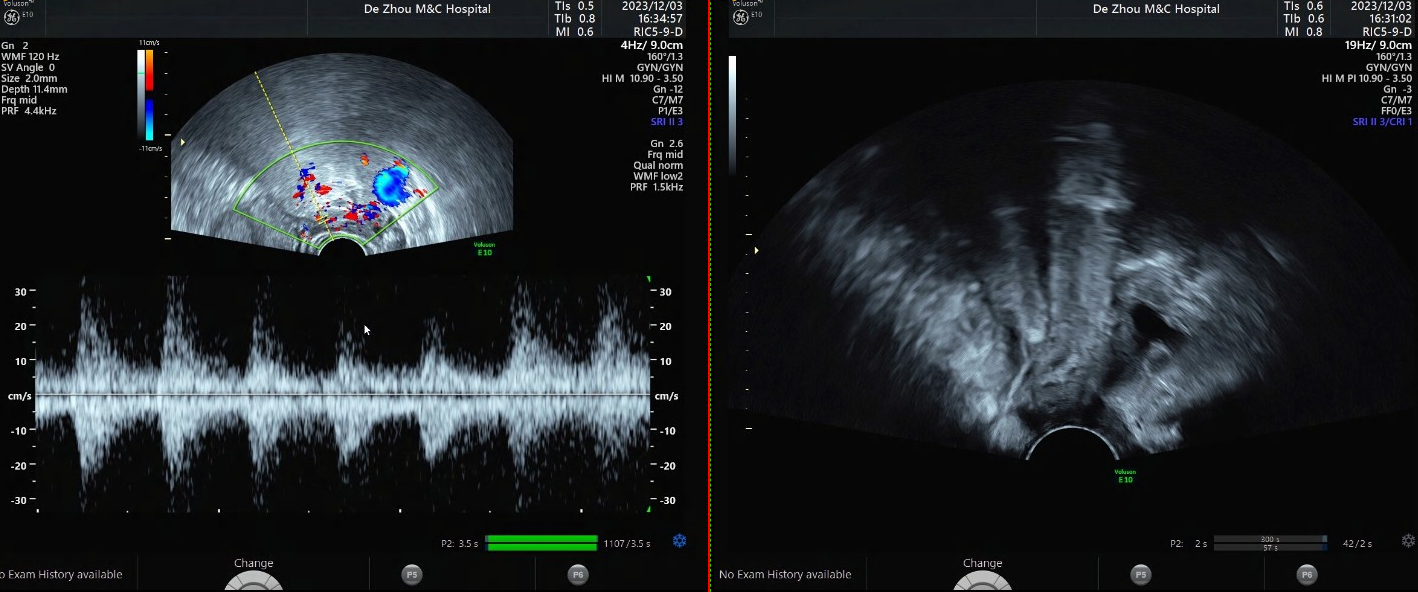

2023-12-03 B超:内膜厚度16mm,回声不均质,内见散在缝隙样无回声,CDFI:未见明显血流信号;左卵巢与子宫之间见17mmx10mm混合回声,内见5mmx3mm无回声,CDFI:周边半环状血流信号;

2023-12-03 急诊β人绒毛膜促性腺激素HCG:938.0 mIU/ml。